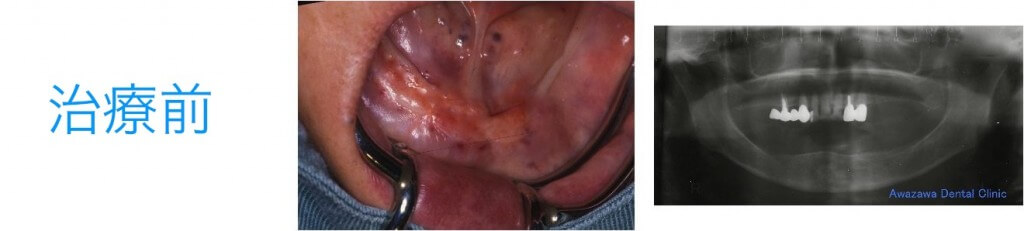

歯根破折により失った下顎の臼歯をインプラントにより修復した症例です。顎の内側に骨の隆起が存在し、この様な場合では義歯による修復は非常に困難でインプラント補綴が有効です。(治療後の写真は治療終了2年経過後の状態です。)